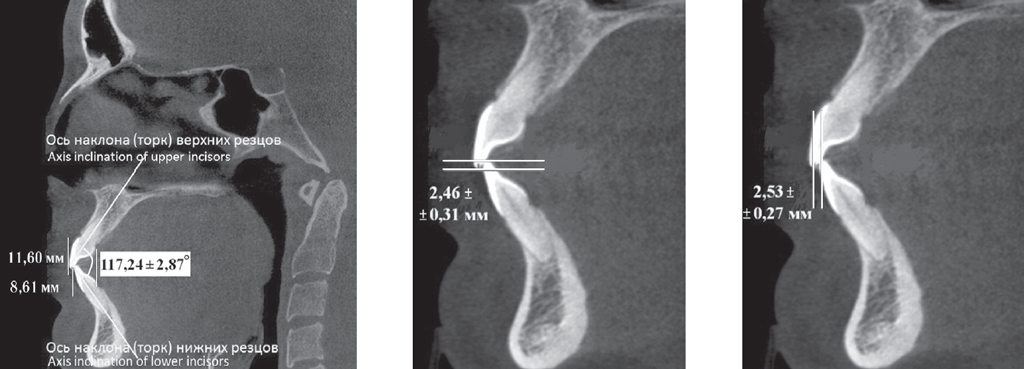

Материал и методы. Обследованы 62 человека первого периода зрелого возраста в двух клинических группах. В 1-ю группу вошли 24 пациента с физиологической окклюзией, а во 2-ю (38 человек) — с патологической окклюзией. В каждой группе были выделены пациенты с протрузией и ретрузией резцов. Вертикальное перекрытие оценивали на томограммах и гипсовых моделях челюстей между горизонтальными линиями, проходящими через режущие края резцов верхней и нижней челюстей параллельно окклюзионной плоскости.

Результаты. У пациентов 1-й группы с протрузией резцов межрезцовый угол составил 149,55 ± 3,92°, торк верхних резцов — 24,36 ± 2,39°. При ретрузии резцов величина межрезцового угла составила 151,47 ± 2,94°, торк верхних резцов — 5,85 ± 1,42°. При этом величина вертикального перекрытия соответствовала величине сагиттального перекрытия и не превышала 2–3 мм. У пациентов 2-й группы, как правило, отмечалось нарушение формы зубных дуг в переднем отделе.

Выводы. Для диагностики физиологической протрузии или ретрузии резцов использовали величины перекрытия в сагиттальном и вертикальном направлениях, которые соответствовали друг другу и не превышали 3 мм.